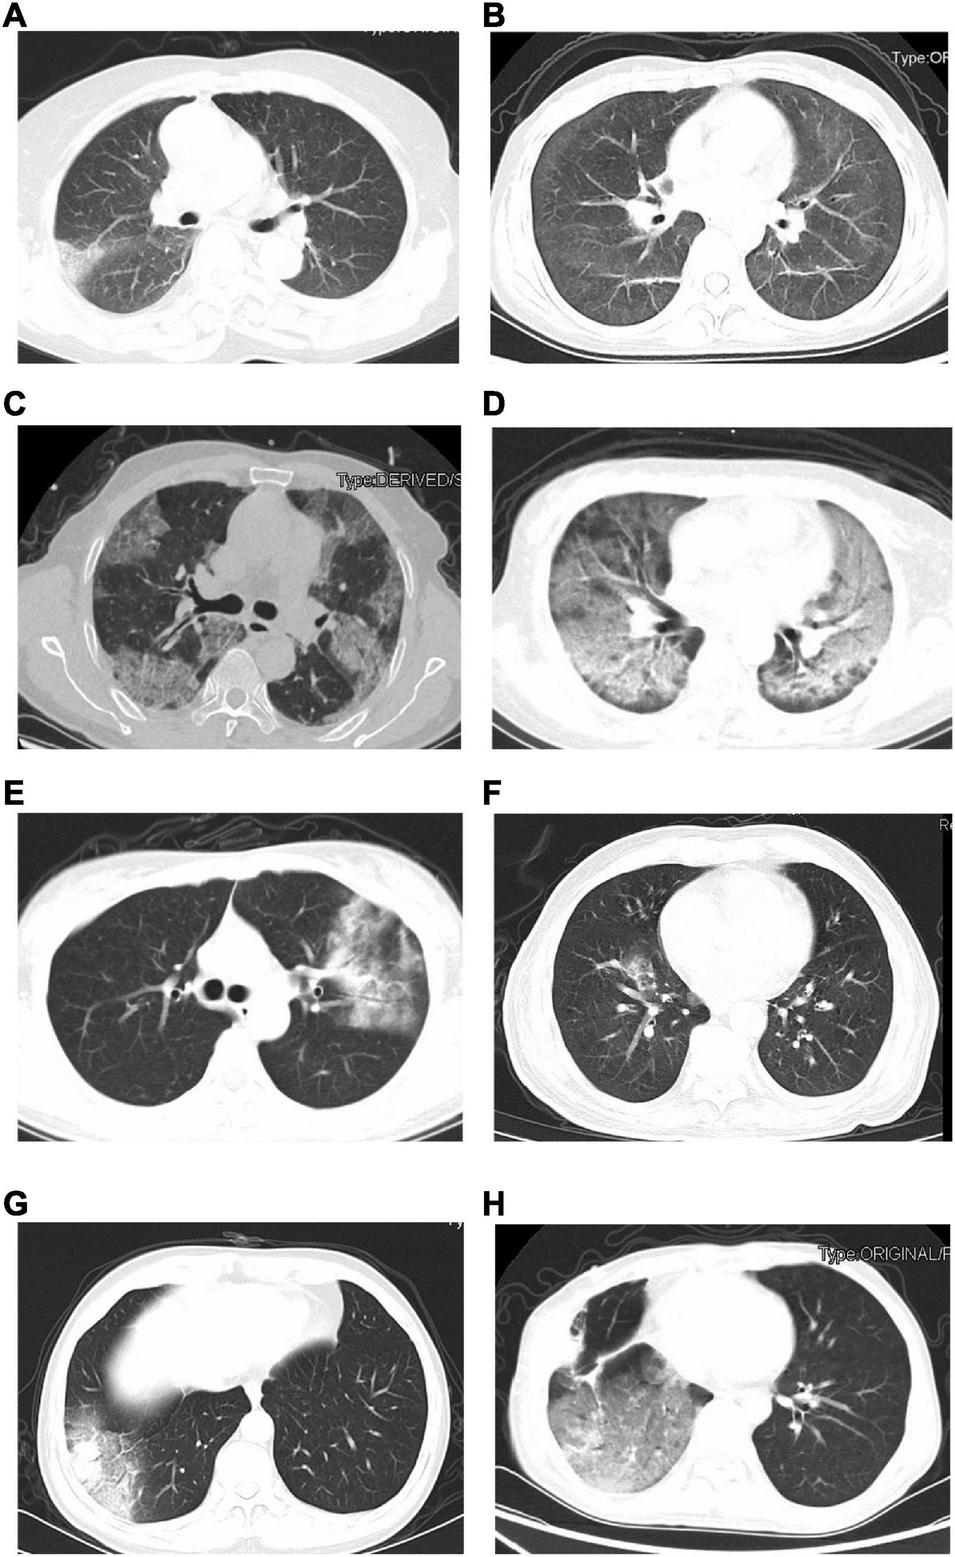

The initial chest CT features of SARS-CoV-2-Negative CAP patients were diverse, as shown in Figure 2. Table 4 showed the detail of chest CT findings in the patients. The most common manifestations were GGO (91/169, 53.85%) and pulmonary nodules (88/169, 52.07%). The most frequently involved lobes were left lower lobe (106/169, 62.72%) and right lower lobe (98/169, 57.99%). More than half of the patients presented multifocal (130/169,76.92%), bilateral (95/169,56.21%) lung lesions. More lesions were inclined to distribute in the bilateral upper lobes and right middle lobe in the emergent viruses positive group than those in the emergent viruses negative group (P = 0.000).

FIGURE 2

The initial chest CT features were diverse in these CAP patients, and the most common manifestations were GGOs and pulmonary nodules in bilateral multiple lungs. Which were similar to the CT imaging features of patients with COVID-19 (Caruso et al., 2020; Xu et al., 2020). The imaging features of virus infections are usually multifocal GGOs. GGO is usually the CT manifestation of pathological diffuse alveolar damage (Chong et al., 2010). A nodular pattern of pneumonia may be seen in various infections (Reittner et al., 2003). Therefore, many patients in our study had pulmonary nodules. This study also found more emergent viruses positive patients have bilateral upper lobes involvement than emergent viruses negative patients. Patients with emergent virus reactivation have low cellular immune function, are more likely to progress to critical disease, and chest imaging lesions are more likely to involve multiple lung lobes. A recent study also showed the level of decreased CD4 + T cell may prompt the severity of CT imaging in patients with COVID-19 (Yang Y. et al., 2020). Due to the physiological anatomy of the lungs, the lesions of most CAP patients tend to occur in the lower lungs, and the upper lungs are less involved. Therefore, the upper lungs of patients with emergent virus reactivation are relatively more frequently involved.